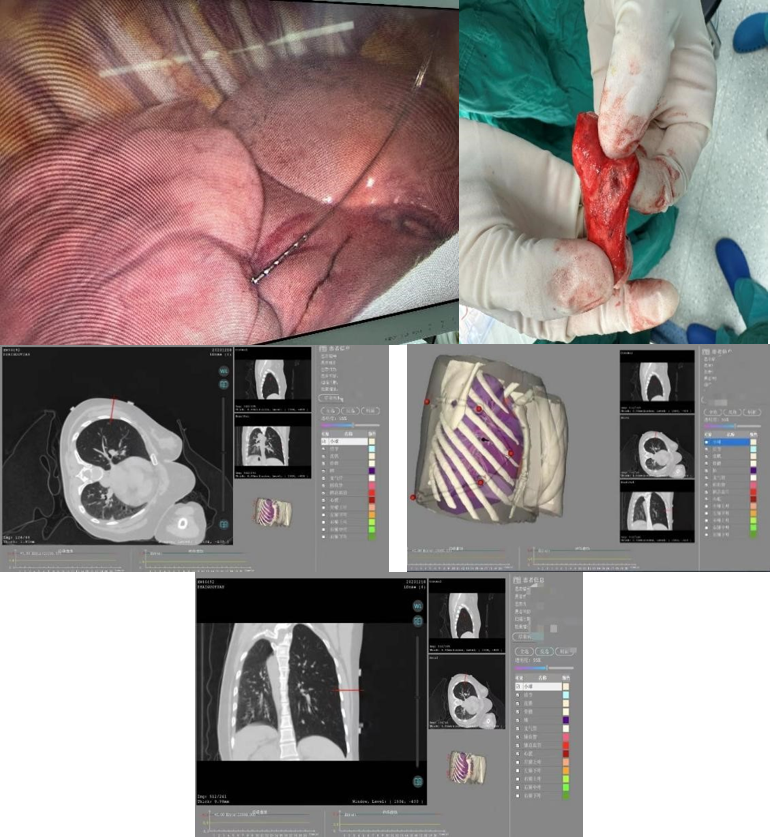

患者右下肺大小8mm的混合磨玻璃结节位于背段气管以上肺组织外三分之一处;另右中肺大小6mm的磨玻璃结节位于水平裂边缘,且患者水平裂发育良好,可直接行右中肺结节楔形切除术。结合患者本人意愿,马海涛教授为其制定右中肺结节楔形切除术及右下肺结节定位后节段切除术的手术方案,精准定位及精准切除的同时,尽最大可能减少患者的肺功能损失。马海涛教授带领其团队充分讨论该患者的定位方案,决定使用“机器人穿刺导航定位系统”为该患者进行术前定位。该技术人机结合,通过病灶提取、路径规划、光学导航、穿刺实施等步骤完成术前定位工作,减少术中肺组织切除范围。相较于传统定位技术,该机器人定位系统在定位安全性、定位准确性、定位稳定性、定位效率上均有所提高,优势显著。

定位过程中,机器人快速的三位重建及路径规划步骤